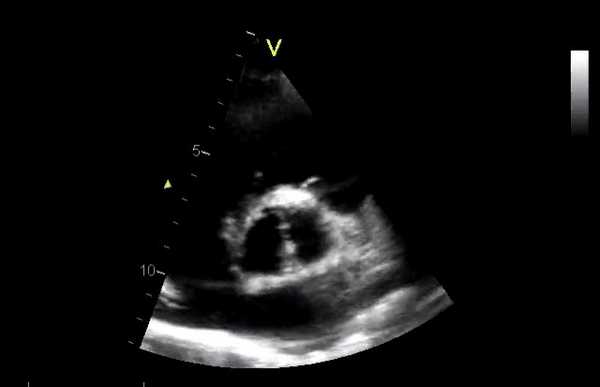

Проведение двухмерной ЭхоКГ дает важную анатомическую информацию.

- Если подробности хирургического вмешательства недоступны, некоторые аспекты эхокардиографического исследования могут помочь определить, какой тип клапана присутствует (легче выполнить эту оценку для митрального, чем для аортальных клапанов):

- Шар и клетка - характерное полукруглое эхо-изображение клетки с шаром, движущимся вверх и вниз

- Наклонный диск - можно увидеть движение одного или двух дисков при открытии и закрытии

- Ткань - металлические стенты (стойки) часто можно увидеть в полости ЛЖ (митральная позиция) или аорте (аортальная позиция).